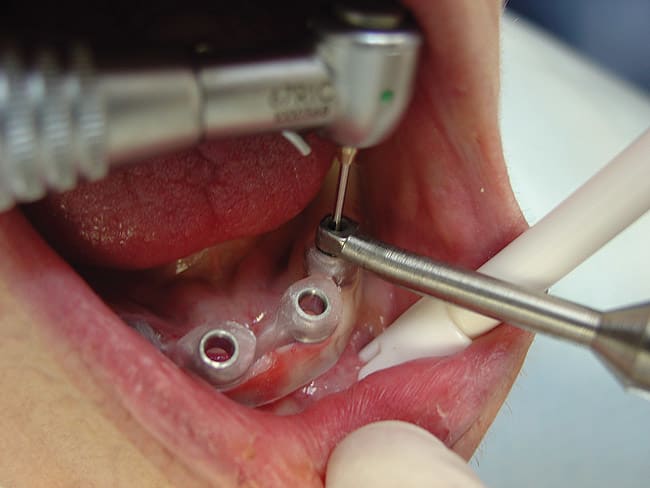

The implant was first removed from its package using either the finger driver or a contra angle adapter. This prevented the sterile surface of the implant from being contaminated. The implant was then inserted into the pilot opening through the surgical stent and gingiva, and into the bone. The implant was slowly rotated clockwise (with a drill or hand instrumentation) using downward pressure until firm, bony resistance was detected. The implant was inserted until all threads were subgingival and the top of the polished collar was flush with the top of the gingiva. At this point the clinician knows that the implant is seated to the proper depth of placement (Figure 7). If extremely dense bone was present, as is often the case in the anterior mandible, a ratchet wrench was used for the final rotations of implant insertion. The ratchet wrenching was done using very slow incremental turns, which allowed full insertion of the implant without implant fracture or stripping of bone. If very heavy resistance was noticed, the implant was removed by rotation in the reverse direction and the pilot hole was made deeper, or a shorter implant was used. Through the entire rotation procedure, pressure was constantly applied on the head of the ratchet in the direction of desired insertion.